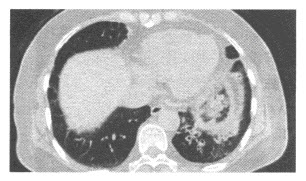

18、单项选择题

男,50岁,胸背剧痛1周余,CT如图,最可能的诊断是()

A.主动脉弓真性动脉瘤

B.主动脉弓假性动脉瘤

C.主动脉弓夹层动脉瘤

D.左上肺癌并侵犯主动脉弓部

E.纵隔肿瘤

191、单项选择题

男,56岁,突感胸闷,憋气,就诊后行CTA检查如下图,应考虑为()

A.主动脉瘤

B.主动脉夹层(DeBakeyⅠ型)并主动脉瘤

C.主动脉夹层(DeBakeyⅡ型)并主动脉瘤

D.主动脉夹层(DeBakeyⅢ型)并主动脉瘤

E.主动脉血栓

192、单项选择题

女性,58岁。突感胸骨后疼痛来院就诊。行胸部CT平扫如图:

A.X线平片

B.胸部超声

C.MSCTA

D.MRI

E.放射性核素扫描